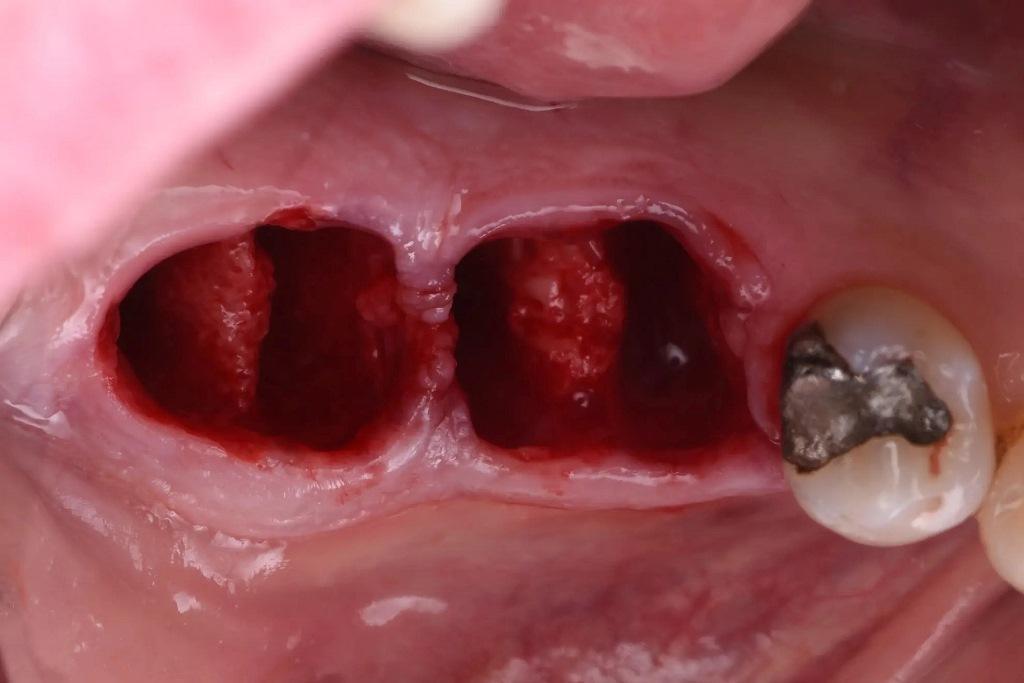

Поврежденные зубы были рассечены и удалены атравматичным способом для сохранения окружающей кости (фото 7). Лунки были тщательно обработаны кюретами Lucas для удаления любой остаточной инфекции или грануляционной ткани (фото 8).

Фото 8: Тщательно обработанные лунки.